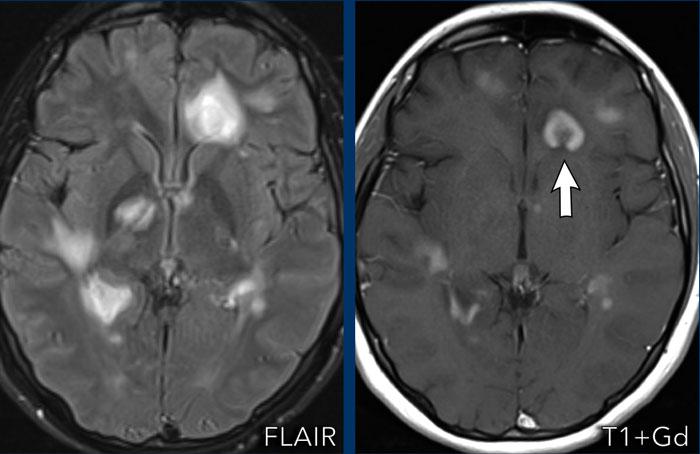

Bệnh nhân này có tiền sử ung thư phổi và nhập viện với các triệu chứng đau đầu và chậm chạp về tâm thần.

Hãy quan sát các hình ảnh trước rồi tiếp tục đọc.

Câu hỏi:

- Các dấu hiệu hình ảnh là gì?

- Chẩn đoán có khả năng nhất là gì?

Hình ảnh

Ghi nhận nhiều tổn thương ngấm thuốc dạng vòng viền liên thông nhau kèm phù não xung quanh ở bán cầu phải.

Vỏ bao tương đối mỏng và đều với hạn chế khuếch tán ở trung tâm.

Có sự lan rộng đến não thất bên phải kèm ngấm thuốc của lớp lót não thất (mũi tên).

Lưu ý thêm hạn chế khuếch tán tại tam giác não thất bên trái.

Nhiều người cho rằng đây là bệnh di căn do tiền sử bệnh, nhưng các dấu hiệu hình ảnh điển hình hơn cho áp xe não kèm viêm não thất, và đây chính là chẩn đoán cuối cùng được xác nhận.